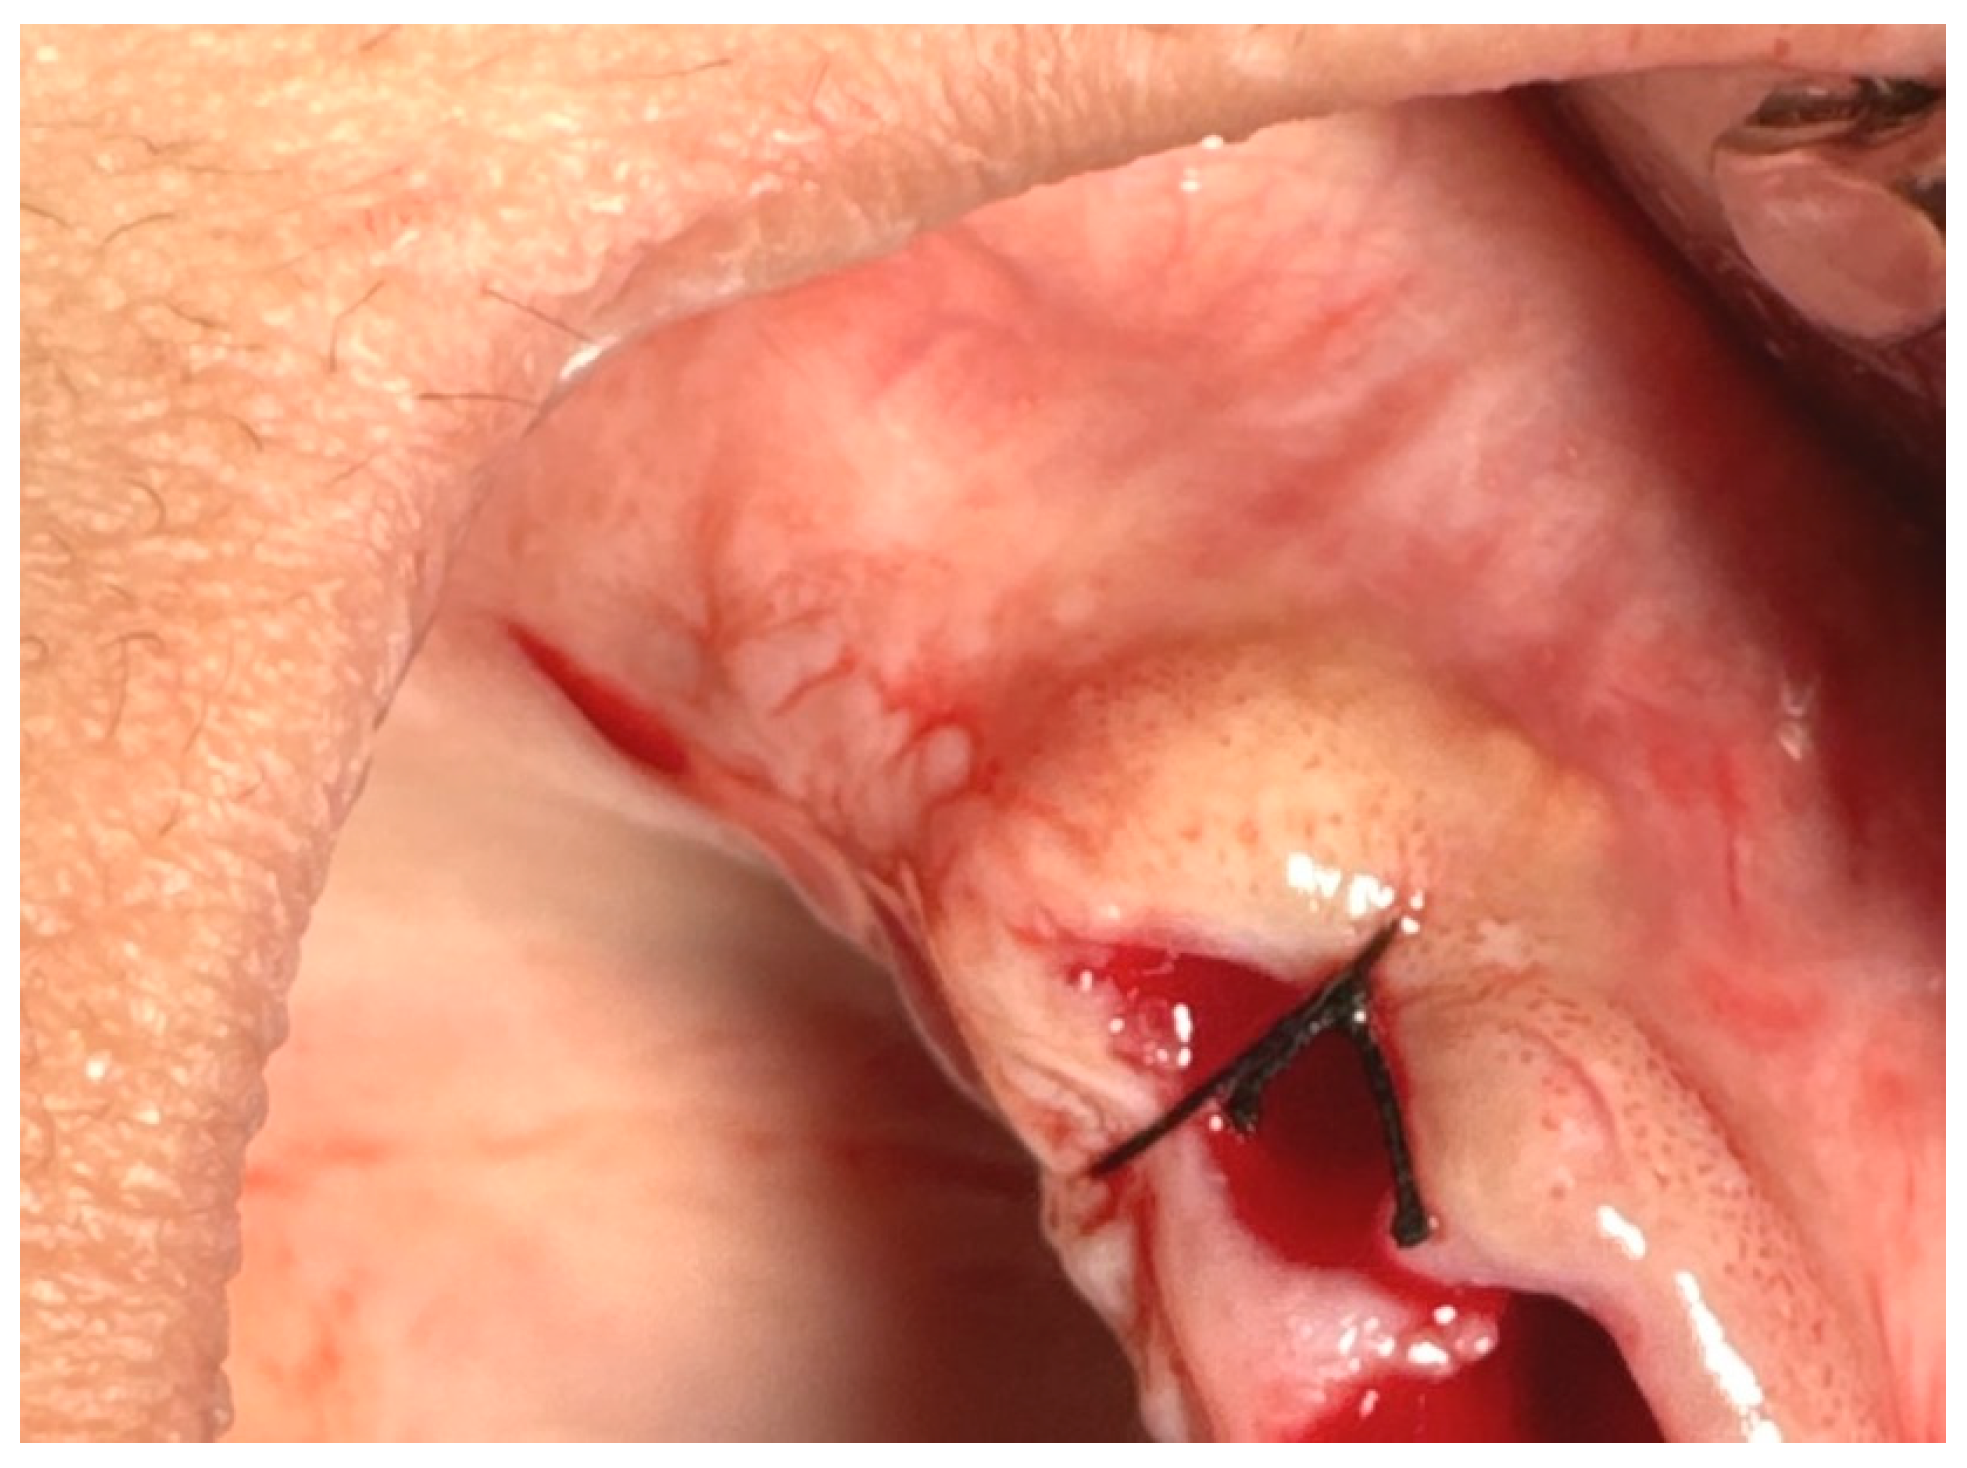

17.2. A horizontal U-shape (mattress) suture is used to assist in local hemostasis after tooth extraction, as shown in Figure 4. It tightens both sides of the wound (closing post-extraction wounds, covering intraosseous implants, etc.) [59,60].

Figure 4. Horizontal U-shape (mattress) suture. Reprinted with permission from Ref. [61]. Copyright 2024 Lax Book: Plovdiv.